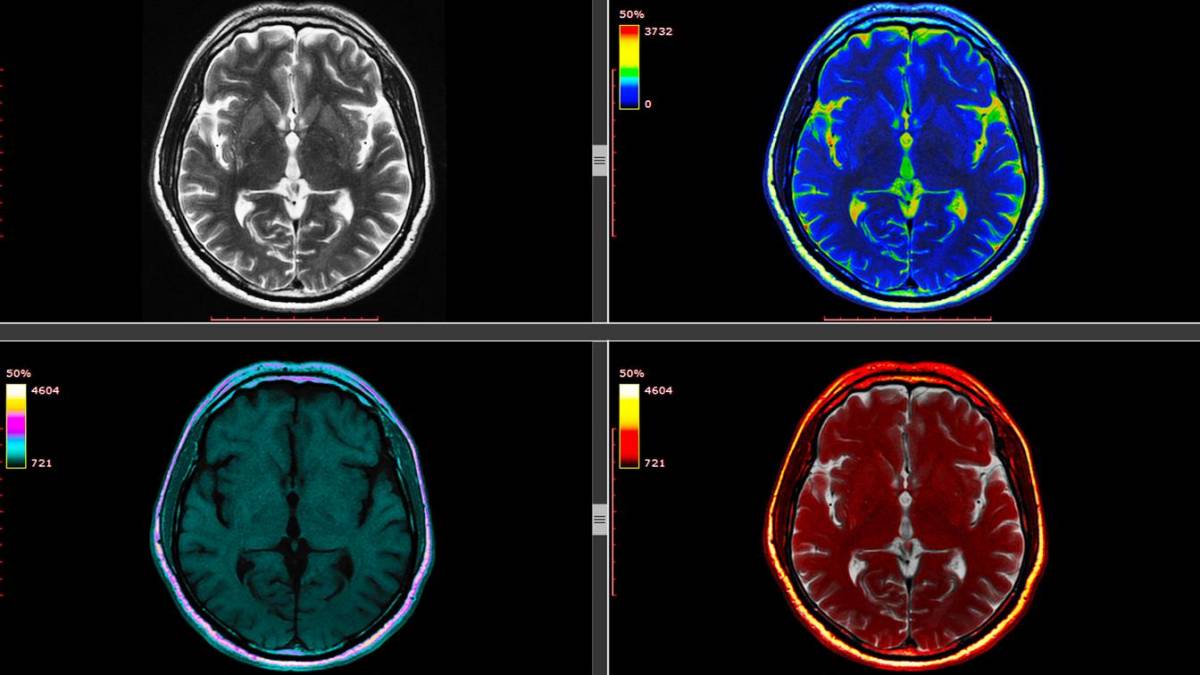

A Intel e a Universidade da Pensilvânia, nos Estados Unidos, querem aplicar uma técnica de aprendizado de máquina criada pelo Google em 2017 para desenvolver uma inteligência artificial que possa identificar tumores cerebrais a partir de exames de imagem.

A empresa de tecnologia e a universidade, junto com outras 29 instituições de saúde e pesquisa dedicadas ao treinamento de modelos de inteligência artificial nos EUA, Canadá, Reino Unido, Alemanha, Suíça e Índia, pretendem usar o maior conjunto de dados de tumores cerebrais já criado para treinar a ferramenta.